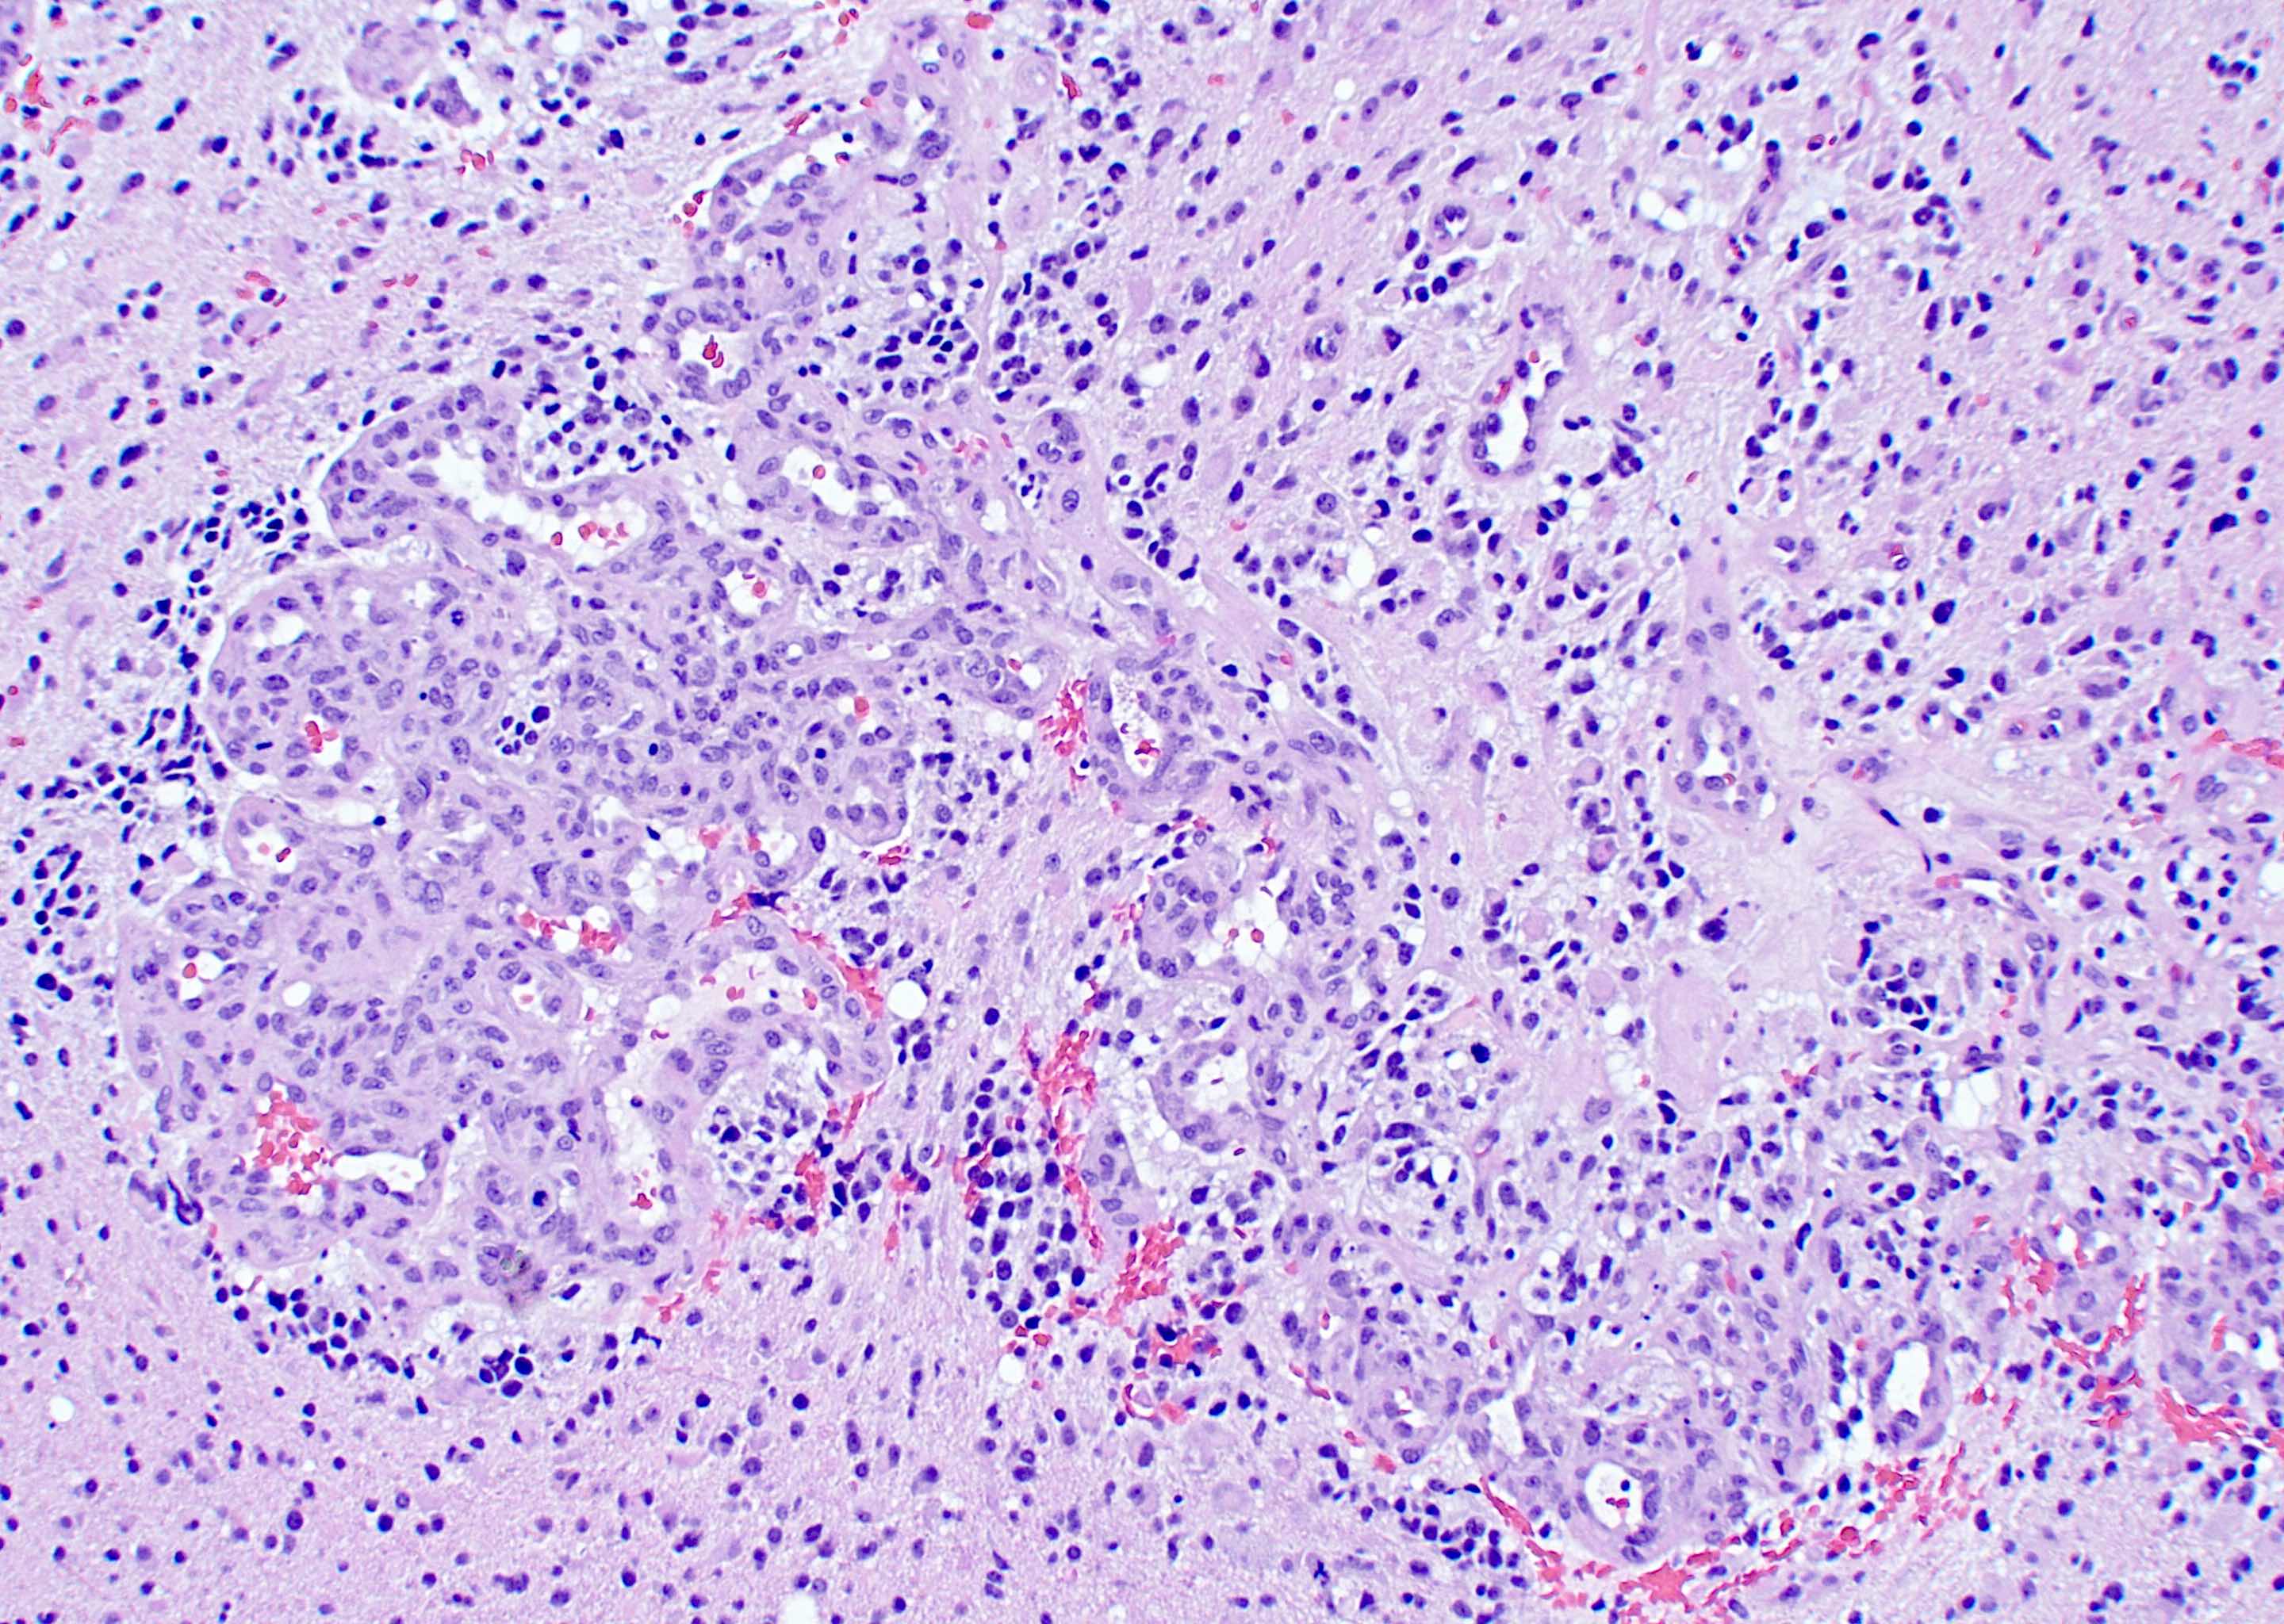

Microscopic (histologic) description

- Infiltrating, hypercellular astrocytic neoplasm often with hyperchromatic, elongated nuclei and irregular nuclear membranes

- Microvascular proliferation or necrosis is required for a histologic diagnosis of GBM

- Microvascular proliferation: multilayered, small caliber vessels with glomeruloid appearance (J Neuropathol Exp Neurol 1992;51:488)

- Necrosis: can be geographic or pseudopalisading with neoplastic cells surrounding central necrosis

- Greater association of thrombosis and necrosis in IDH wild type GBM than in IDH mutant grade 4 astrocytomas (Acta Neuropathol 2016;132:917)

Microscopic (histologic) images

Contributed by Bharat Ramlal, M.D. and Meaghan Morris, M.D., Ph.D.